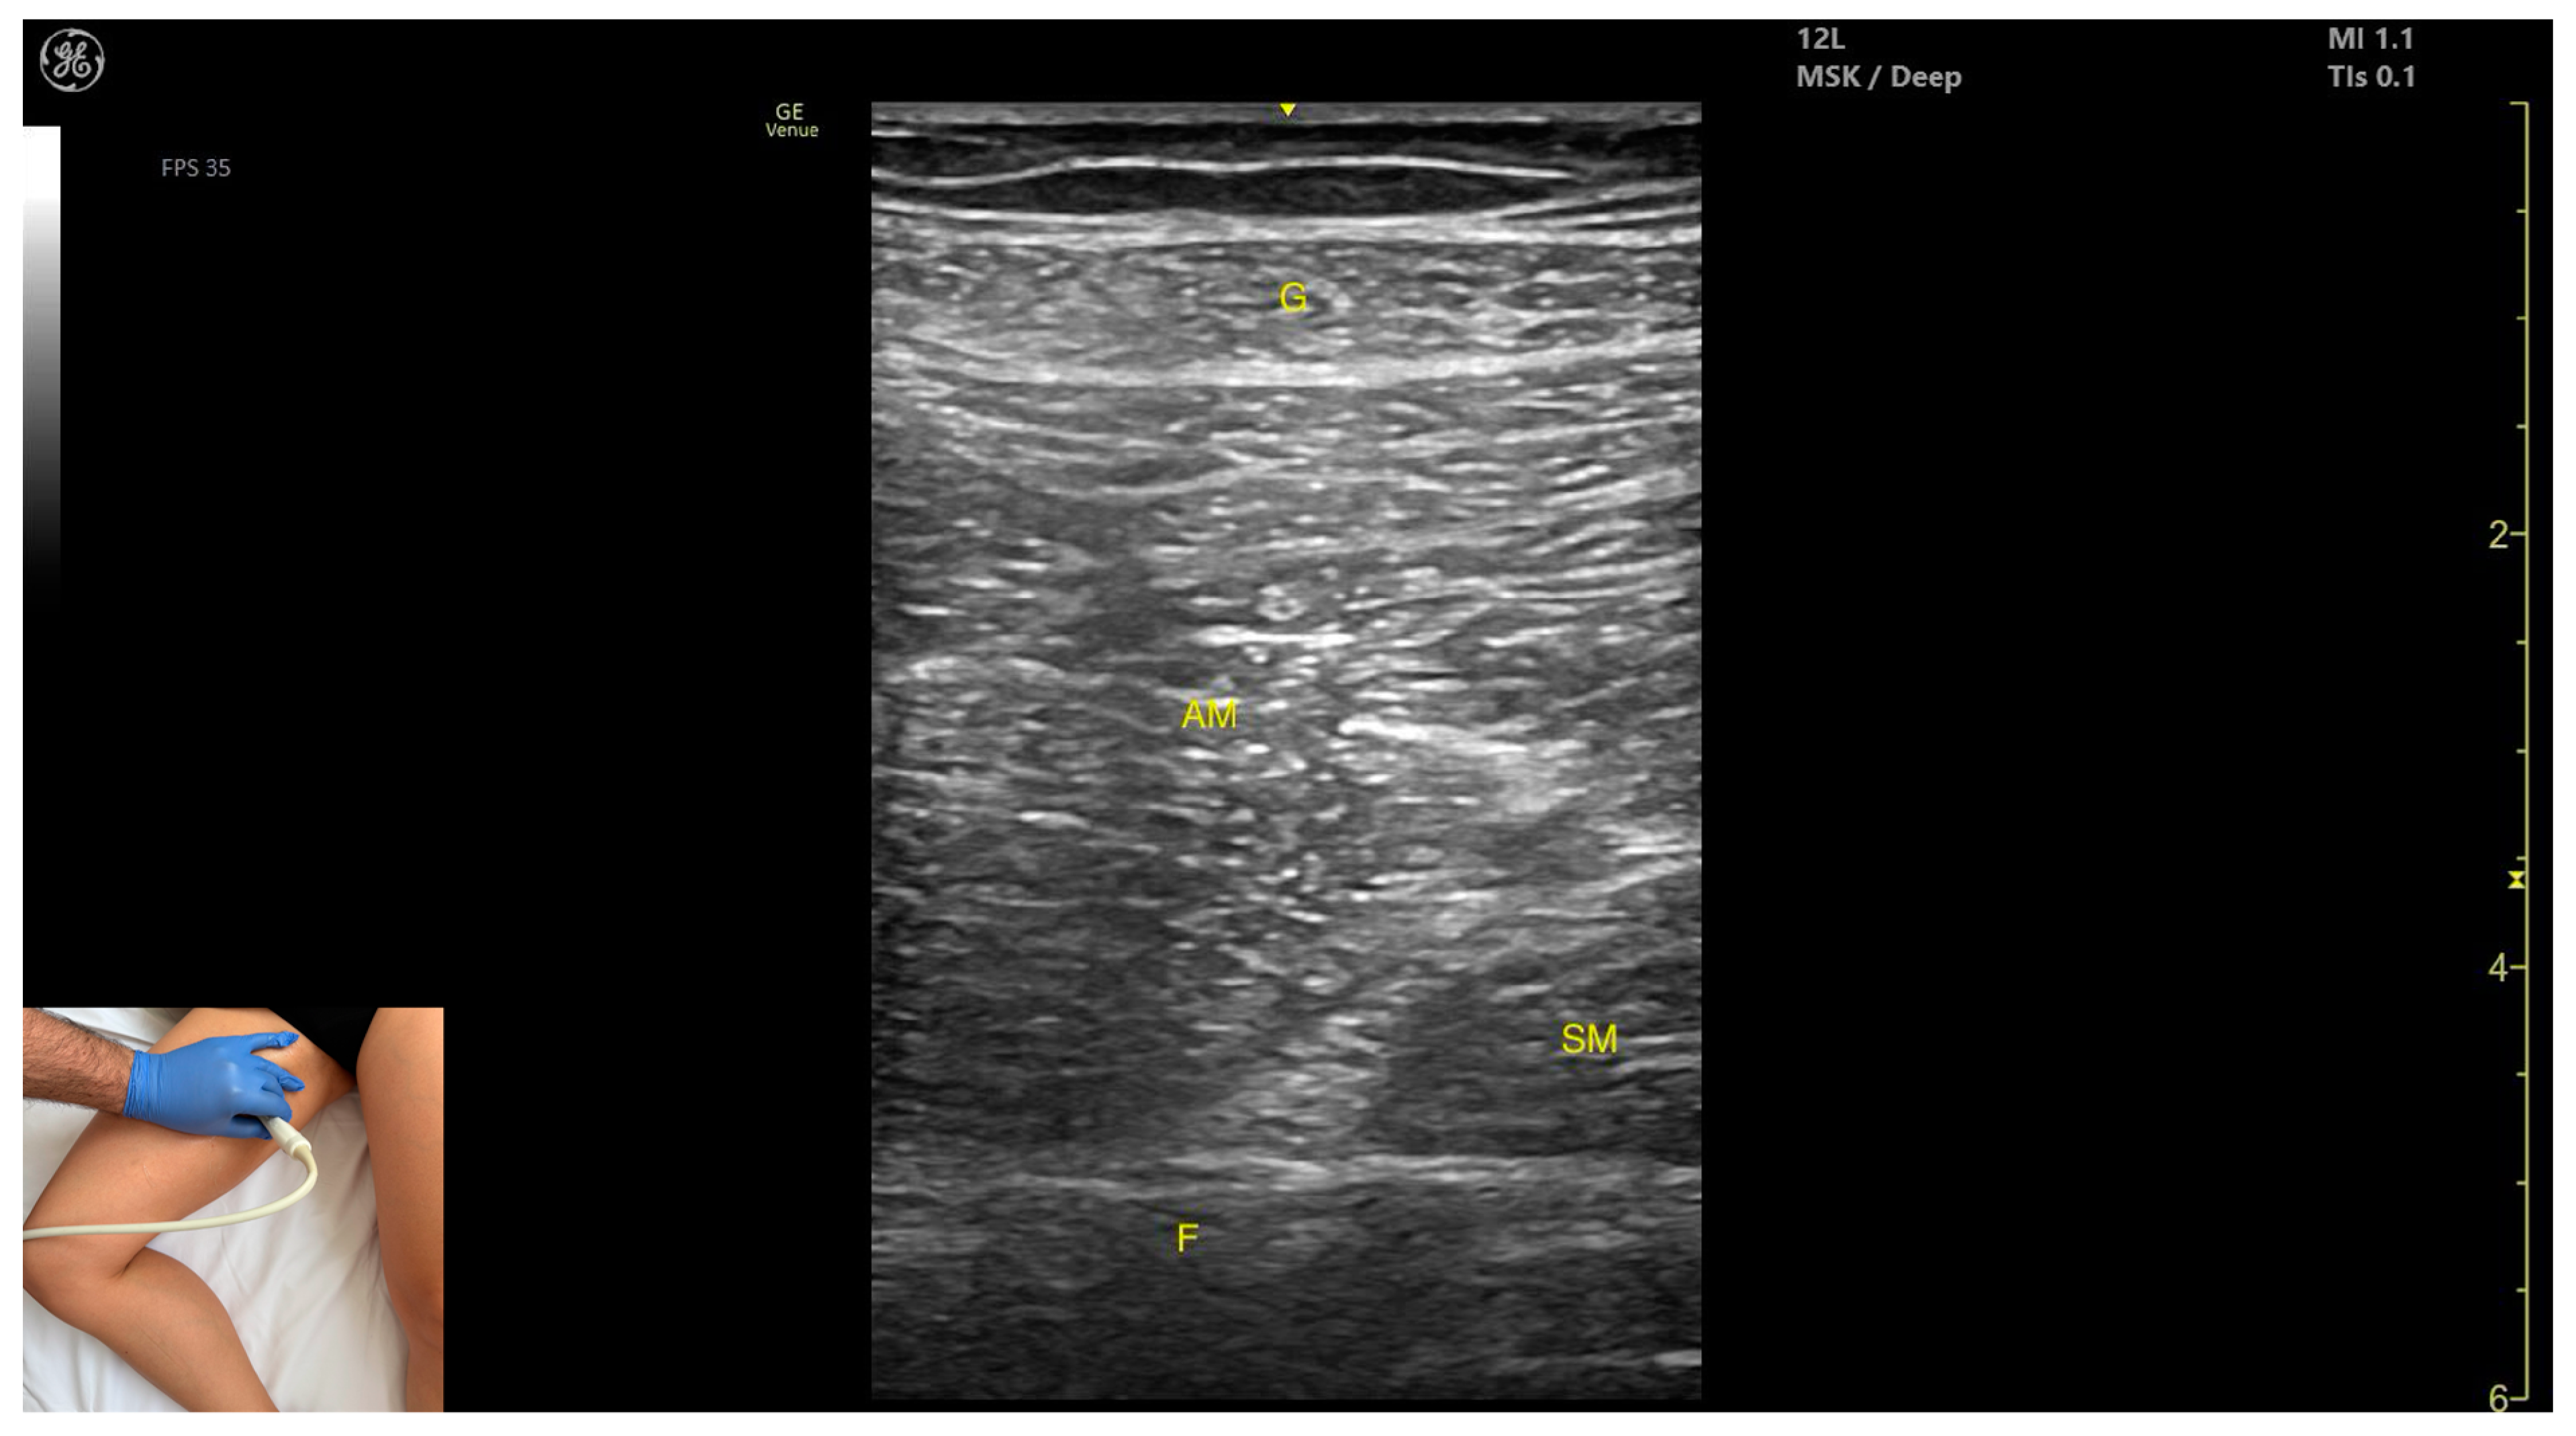

3.6. Gracilis (G)

3.6.3. Key Ultrasound Landmarks

- Muscle position: It is the most superficial and medial muscle mass of the thigh. Lateral and deep to the G lies the adductor longus, while medial and deep to the G lies the semimembranosus.

- External fascia: It presents a well-defined fascia that separates it from the subcutaneous plane and from the adductor magnus, adductor longus, and semimembranosus, which is relevant for BoNT-A injections.

- Dynamic evaluation: During dynamic evaluation, scanning toward the distal third of the medial thigh, the following are observed: the relationship between the G and adductor magnus remains consistent, the adductor longus disappears from view, the Sart muscle appears, joining the gracilis, and the adductor canal becomes visible, located deep and lateral to the gracilis. In the distal third of the medial thigh, the G is positioned lateral to the semitendinosus. Scanning further distally beyond the knee joint, the tendons of the G, sartorius, and semitendinosus converge to form the pes anserinus on the medial aspect of the proximal tibia. Muscle contraction is visible during hip adduction, knee flexion, and internal rotation maneuvers.

3.6.4. Clinical Implications and Injection Strategy

| G | Gracilis (muscle) |

| Gracilis | Proximal third of medial thigh | Adductor longus (deep and lateral), adductor magnus (deep), and semimembranosus (deep and medial) | Transverse scan with the hip abducted, externally rotated, and semi-flexed and the knee in semi-flexion | Visualize gracilis as most superficial medial muscle |